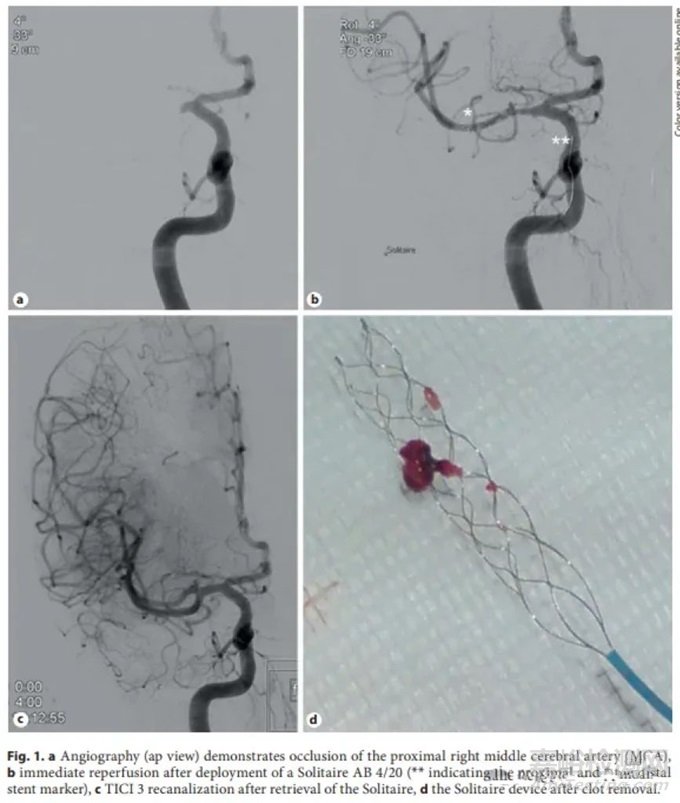

Solitaire:Solitaire FR(血流恢復(fù))支架取栓器(Covidien/Medtronic,Dublin, Ireland)是第一個專用的血栓切除支架。之前有一種Solitaire AB(動脈瘤輔助)器械,用于建立臨時通路和取栓。

當(dāng)前器械是第四代Solitaire X。它是一種鎳鈦合金支架,由鎳鈦合金片激光切割并成型為重疊的參數(shù)設(shè)計。幾何配置為閉合單元設(shè)計,具有頂點-頂點連接(如下圖)。支架有3、4和6 mm直徑可用,3 mm直徑的支架長度為20 mm,4 mm直徑的支架長度為20和40 mm,6 mm支架的長度為20、24和40 mm。支架在近端和遠端以及支架長度上均勻間隔5-10 mm處均有鉑金標記,用于可視化支架的打開和血栓整合。

參數(shù)設(shè)計導(dǎo)致支架覆蓋重疊,增加了血栓接觸。支架施加的徑向力也取決于血管直徑。

動物研究顯示Solitaire FR器械在移除血栓方面取得了高度成功。在100%的病例中觀察到TICI 3血流恢復(fù),并且在大多數(shù)病例中實現(xiàn)了立即血流恢復(fù)。

單中心經(jīng)驗顯示,該器械在79%的前循環(huán)病例中實現(xiàn)了首次通過再通(TICI 2b/3),整體成功再通率為72.8%。另一項研究顯示,使用Solitaire器械的再通率為89%。初步研究中的并發(fā)癥率較低,腦內(nèi)出血率為2%,蛛網(wǎng)膜下腔出血率為4-6%。